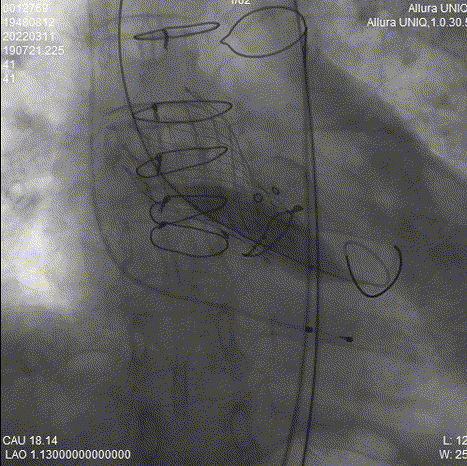

瓣膜释放过程

球囊后扩

瓣膜最终形态